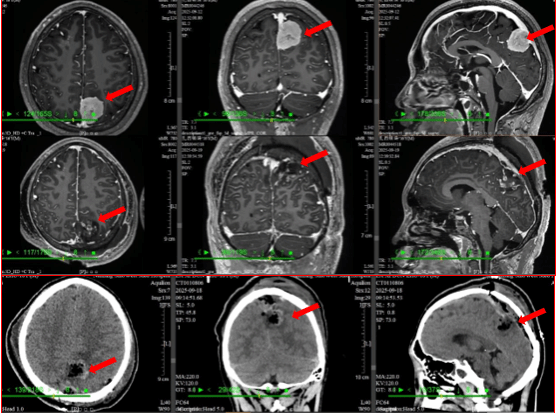

毫米之间的民族团结:粤藏医生共战罕见脑瘤

近日,一位来自西藏林芝的16岁罕见脑膜瘤患者小扎西在中西医结合医院神经外科成功接受了顶叶矢状窦旁脑膜瘤切除手术治疗,康复情况良好。这场跨越三千里的医疗救救治不仅是个案成功,更是粤藏两地医疗协作的典范。援藏一年,以精湛医术赢得信赖2024年,中西医结合医院医生张建锋积极响应号召,前往西藏林芝开展为期一年的医疗支援工作。在海拔三千米的高原上,他克服缺氧等困难,不仅将…